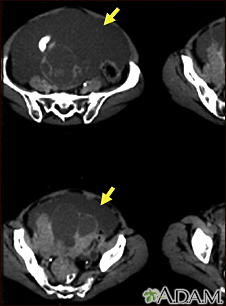

Ascites with ovarian cancer - CT scan

This CT scan of the lower abdomen shows a massive amount of free abdominal fluid (ascites) in a patient with ovarian cancer.